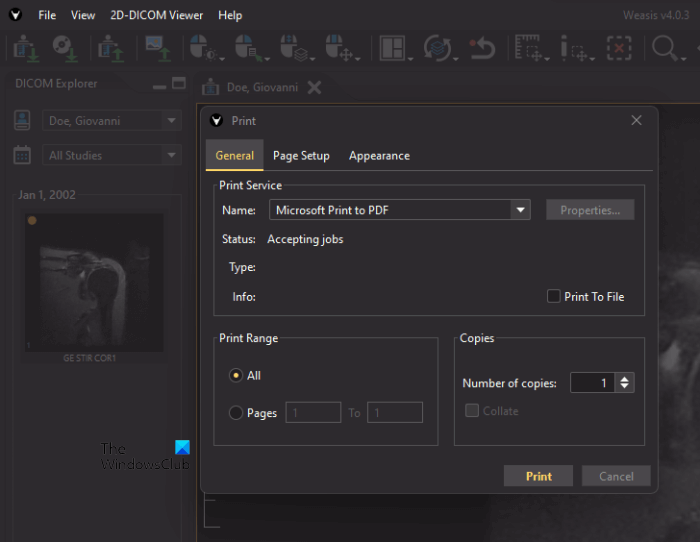

2] Weasis

Weasis is another free DICOM image viewer software that lets you view and analyze DCOM images. It provides users with different options to analyze the DICOM images. You can import DOCIM images to the software either from your computer or from a DICOM CD. After importing the DICOM image, you can easily save it as a PDF by using the Print feature.

The following steps will help you convert a DICOM image into a PDF using Weasis:

- Go to “File > Print > Print 2D viewer layout.”

- Now, select the image position and image DPI from the drop-down menus.

- If you want to print the DICOM image with annotations, check the respective box; otherwise leave it empty.

- When you are done, click Print.

- Select Microsoft Print to PDF from the drop-down and click Print.

- Now, save the file on your computer.

To download Weasis, visit sourceforge.net.